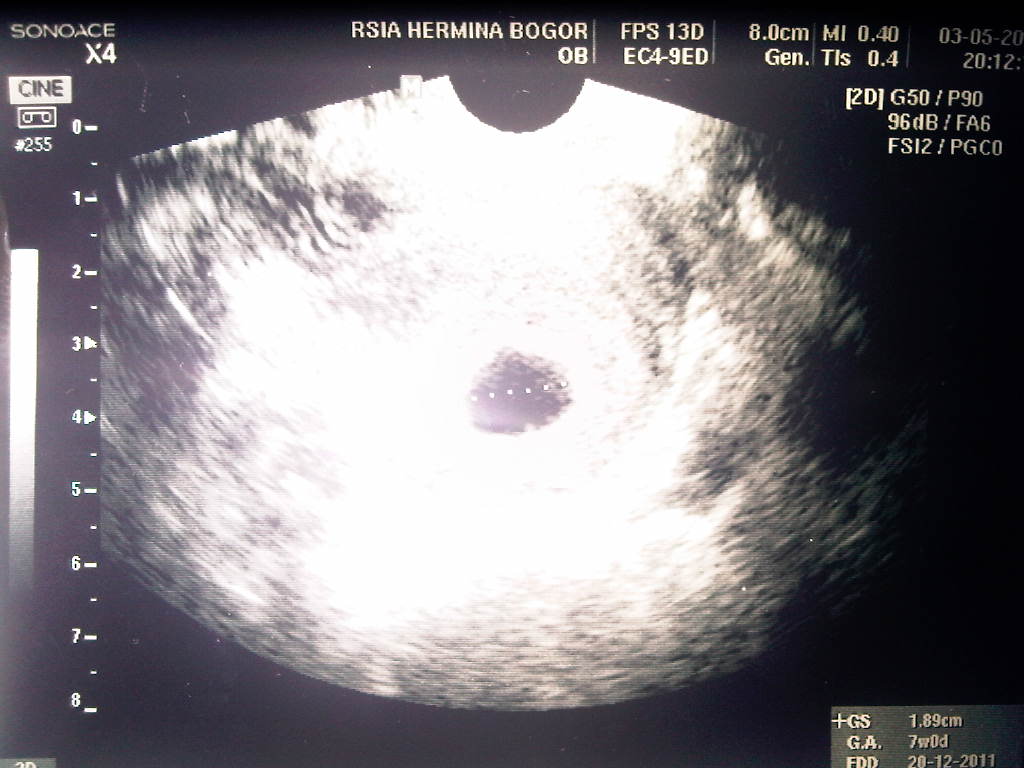

Cek pertama, taunya sudah 7 minggu, sudah kelihatan pertumbuhannya